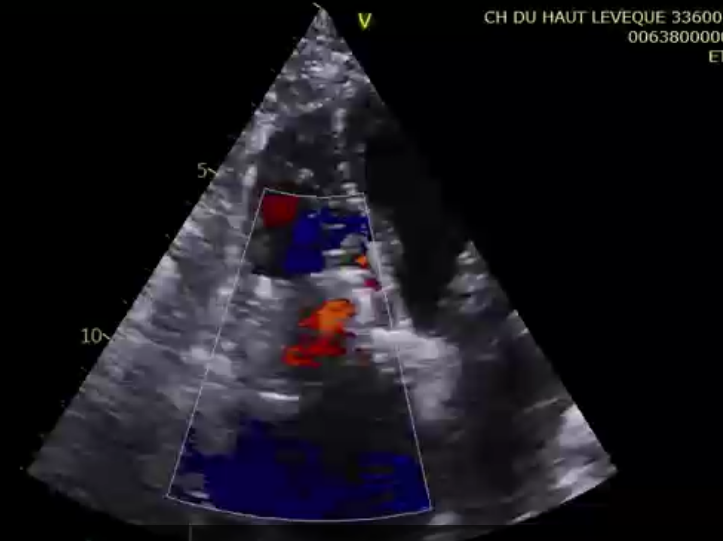

術(shù)前超聲提示大量三尖瓣反流